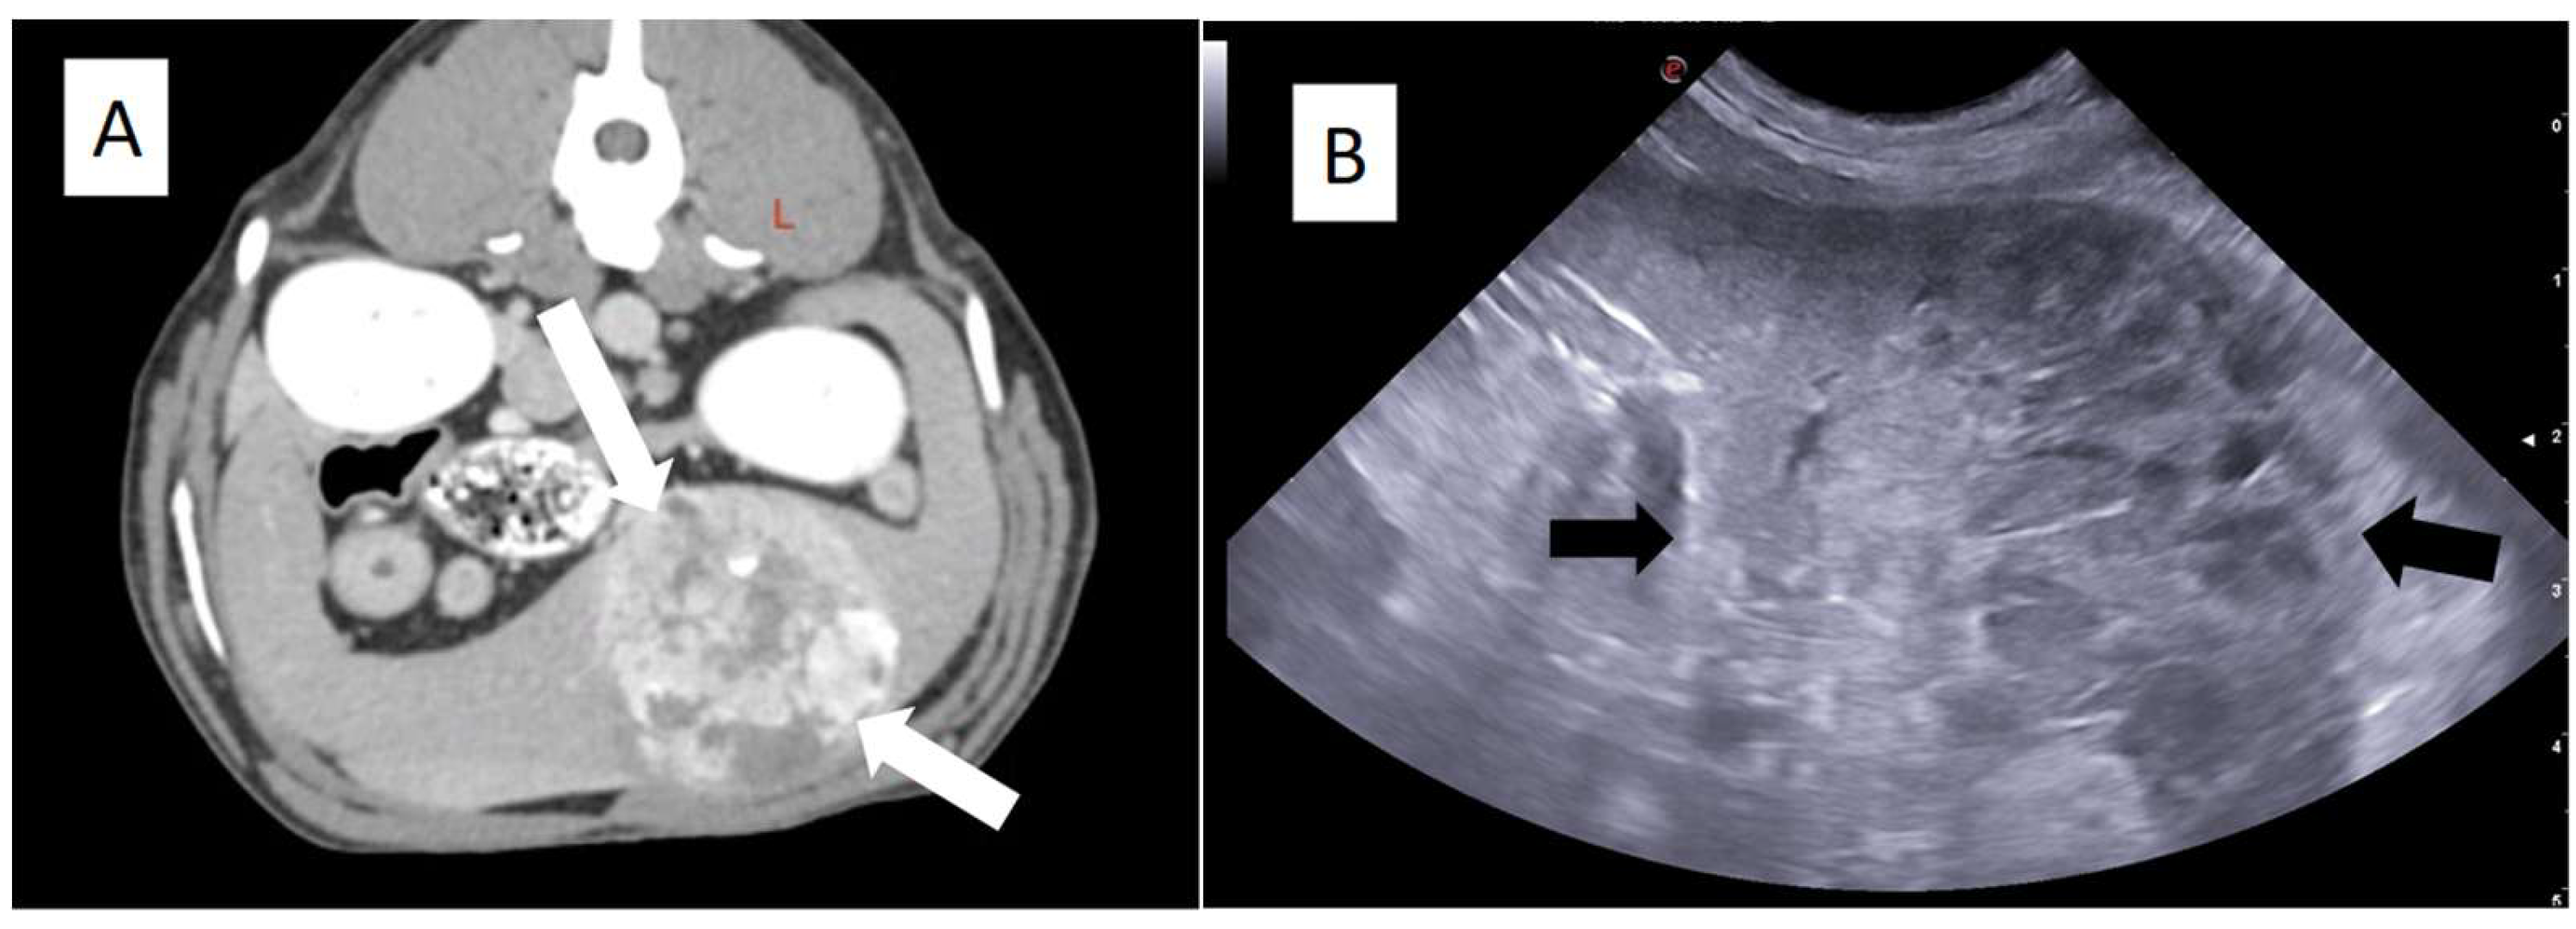

3. Clinical Presentation and Diagnostic Challenges